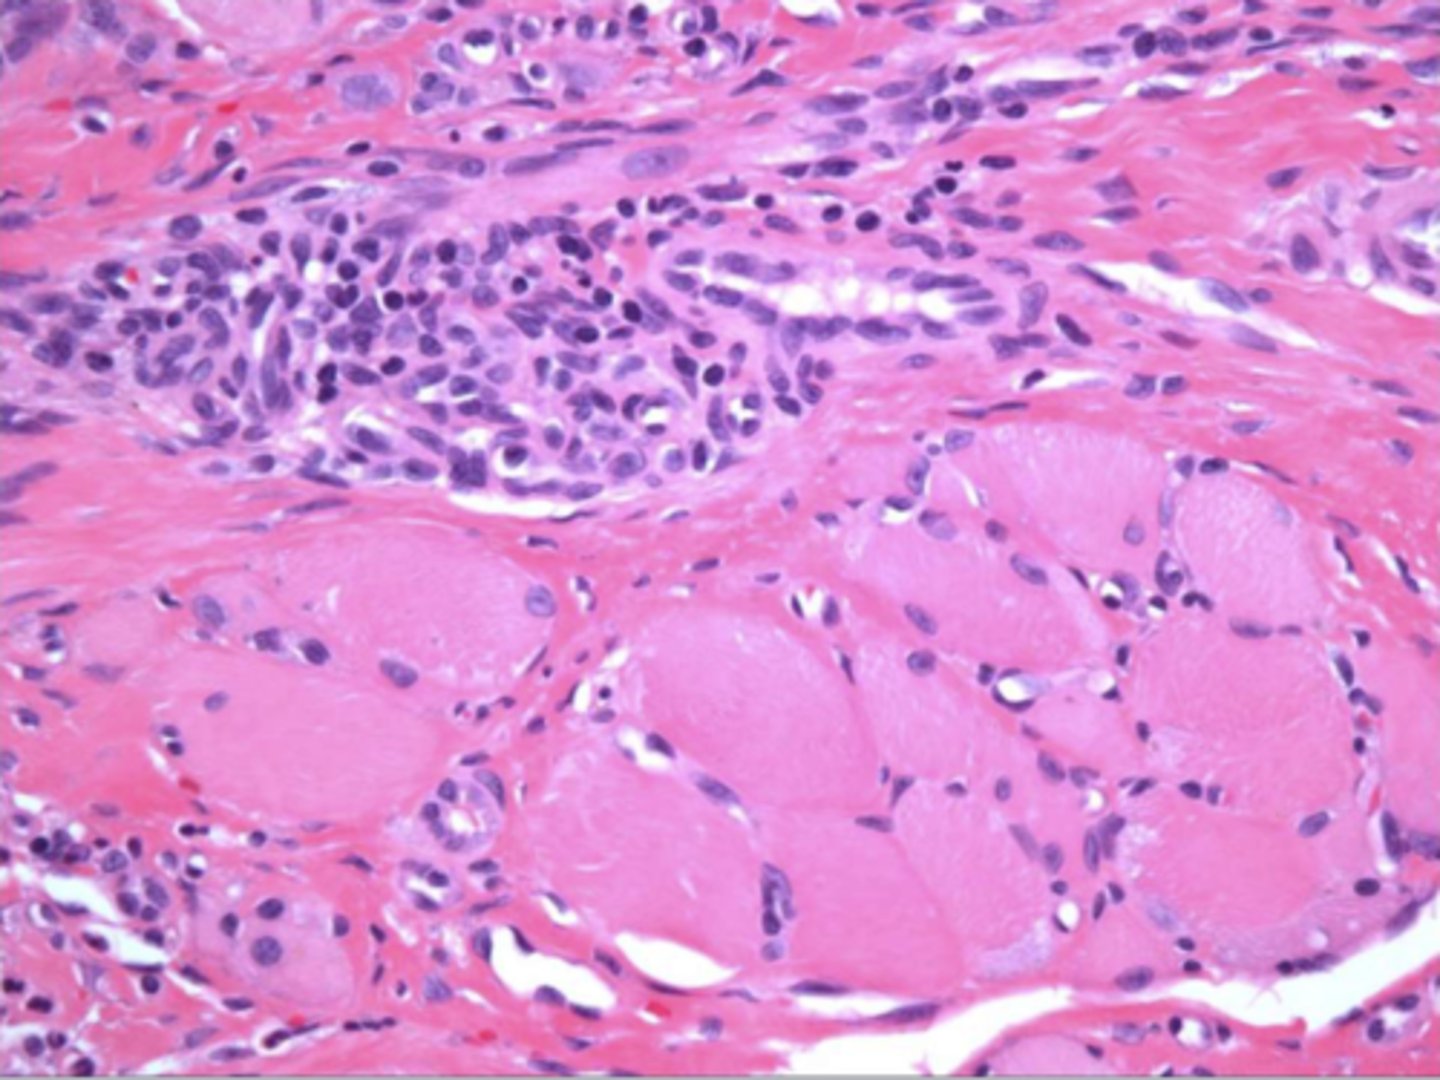

This is a histological image of what?

MRONJ